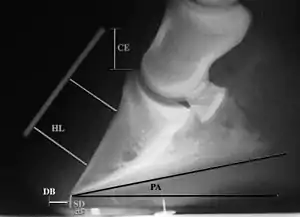

Radiographic measurements, including coronary extensor distance (CE), horn:lamellar distance (HL), sole depth (SD), digital breakover (DB), and palmar angle (PA)

Several radiographic measurements, made on the lateral view, allow for objective evaluation of the episode.

1. Coronary extensor distance (CE): the vertical distance from the level of the proximal coronary band to the extensor process of P3. It is often used to compare progression of the disease over time, rather than as a stand-alone value. A rapidly increasing CE value can indicate distal displacement (sinking) of the coffin bone, while a more gradual increase in CE can occur with foot collapse. Normal values range from 0–30 mm, with most horses >12–15 mm.[1]

2. Sole depth (SD): the distance from the tip of P3 to the ground.

3. Digital breakover (DB): distance from the tip of P3 to the breakover of the hoof (dorsal toe).[1]

4. Palmar angle (PA): the angle between a line perpendicular to the ground, and a line at the angle of the palmar surface of P3.

5. Horn:lamellar distance (HL): the measurement from the most superficial aspect of the dorsal hoof wall to the face of P3. 2 distances are compared: a proximal measurement made just distal to the extensor process of P3, and a distal measurement made toward the tip of P3. These two values should be similar. In cases of rotation, the distal measurement will be higher than the proximal. In cases of distal displacement, both values will increase, but may remain equal. Therefore, it is ideal to have baseline radiographs for horses, especially for those at high-risk for laminitis, to compare to should laminitis ever be suspected. Normal HL values vary by breed and age:[1]

• Weanlings will have a greater proximal HL compared to distal HL

• Yearlings will have approximately equal proximal and distal HL

• Thoroughbreds are usually 17mm proximally, and 19mm distally

• Standardbreds have been shown to have a similar proximal and distal HL, around 16 mm at 2 years old, and 20 mm at 4 years old

• Warmbloods have similar proximal and distal values, up to 20 mm each

• HL tends to increase with age, up to 17 mm in most light breeds, or higher, especially in very old animals